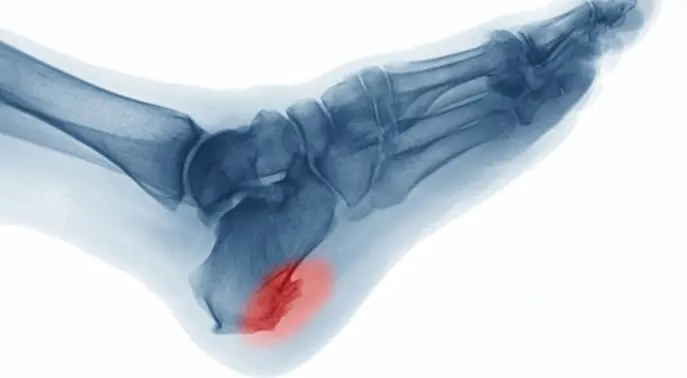

مسمار كعب القدم هو نمو عظمي صغير يشبه المسمار أو النتوء، يتكون نتيجة ترسبات كلسية زائدة في الجزء السفلي من عظم الكعب (العقب). يمكن أن يمتد هذا النتوء من كعب القدم إلى منتصف قوس القدم، ويظهر بوضوح عند تصوير المنطقة بالأشعة السينية (X-ray).

يتشكل هذا النتوء العظمي تدريجيًا على مدى فترة طويلة، ويبلغ حجمه عادة حوالي 1.25 سنتيمتر. يُعرف أيضًا باسم “مهماز العظم”، وقد يكون حادًا ومدببًا أو مسطحًا بعض الشيء.